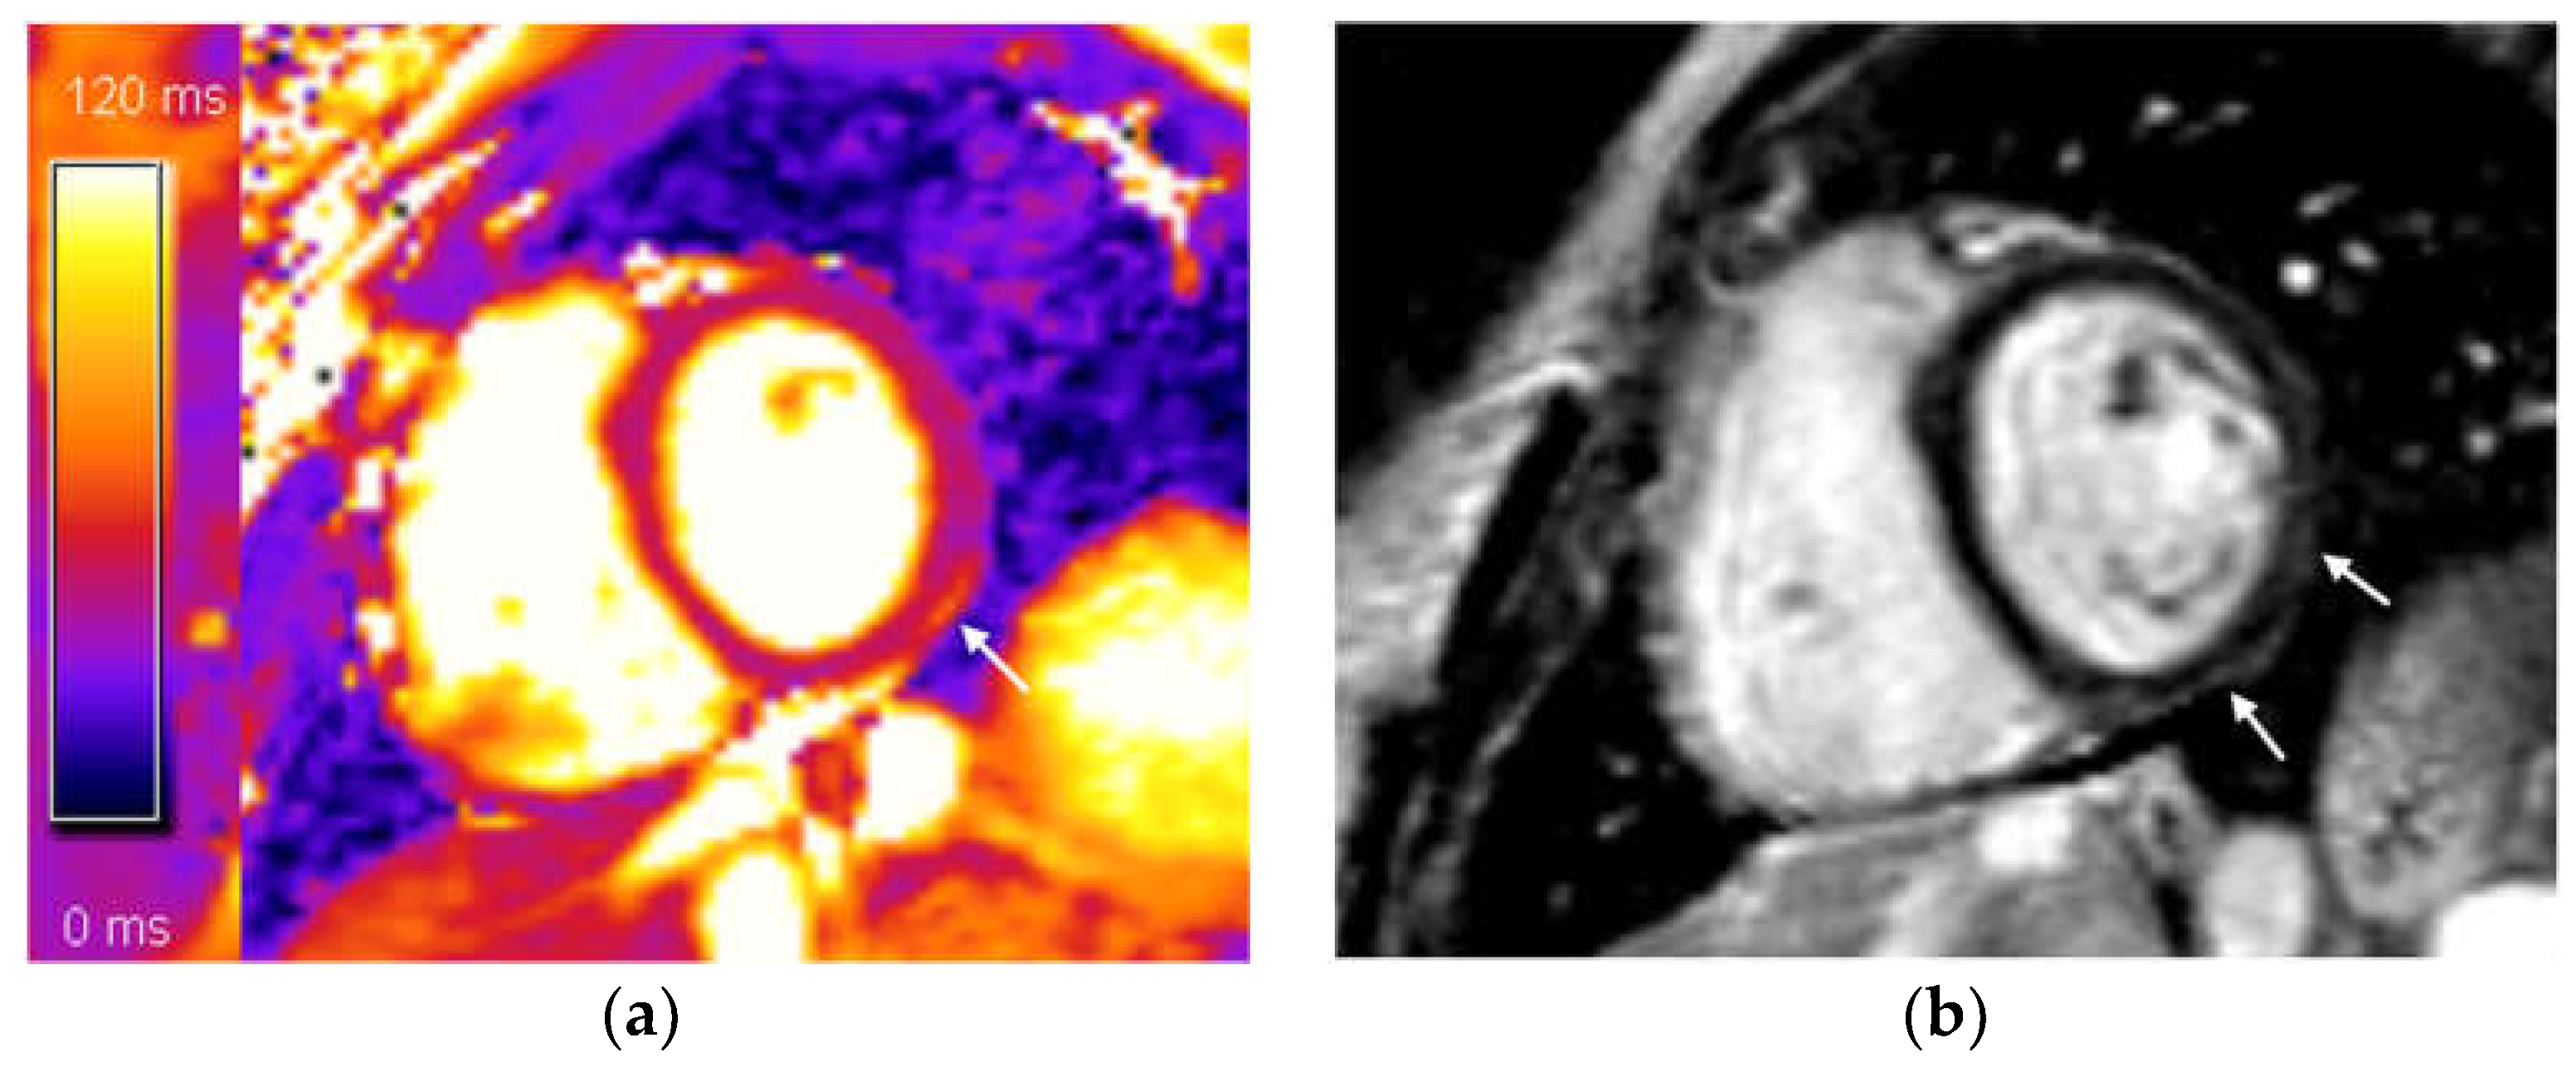

| Mean native T1 value (diffuse), mean ± sd | 1020 ± 35 |

| Mean T2 value (diffuse), mean ± sd | 47 ± 3 |

| Highest mean native T1 value (focal), mean ± sd | 1174 ± 106 |

| Highest mean T2 value (focal), mean ± sd | 58 ± 9 |